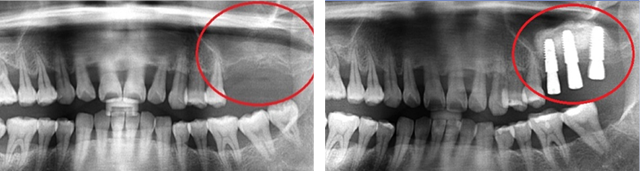

잇몸뼈가 녹아내려 임플란트 12개 진단을 받고 내원한 환자, 고운미소에서 치주치료를 시행한 결과 전치부 잇몸이 개선되어 발치 하지 않고 크라운으로 수복하였고, 어금니에 6개의 임플란트를 식립하였습니다.

잇몸 염증으로 치조골 손실이 많은 상태

잇몸건강이 회복된 앞니는 크라운으로 수복